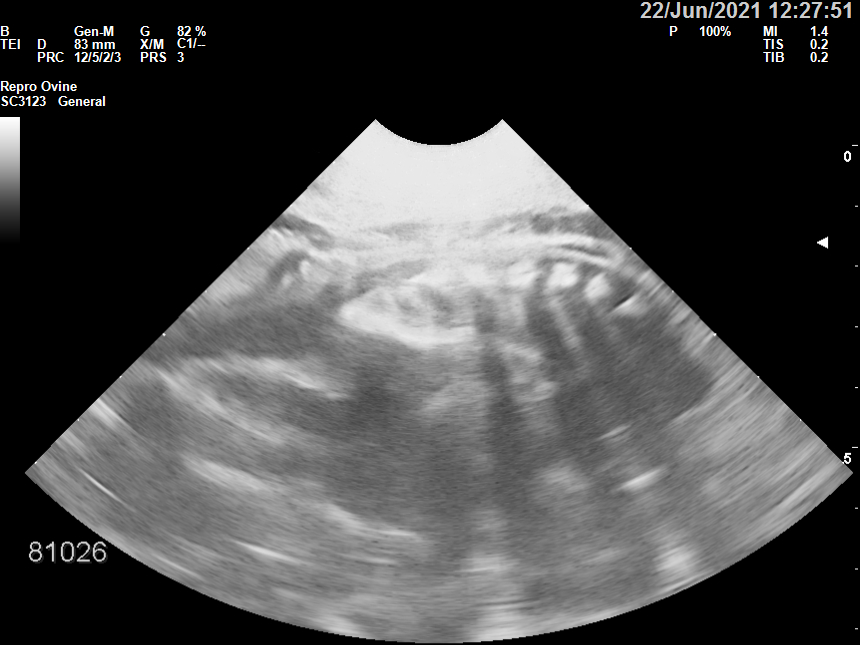

Η υπερηχοτομογραφία αποτελεί βασική μέθοδο διαγνωστικής απεικόνισης της εσωτερικής δομής ενός (εν ζωή) ζώου, που βασίζεται στην αξιοποίηση των υπερηχητικών κυμάτων. Είναι μία μη-επεμβατική μέθοδος χωρίς παρενέργειες, δεν χρησιμοποιεί ηλεκτρομαγνητική ακτινοβολία κάτι που τη καθιστά ασφαλή ακόμη και στα μικρά ζώα. Έχει καλή διακριτική ικανότητα και δημιουργεί εικόνες υψηλής ανάλυσης, σε πραγματικό χρόνο. Πραγματοποιείται από εξειδικευμένο κτηνίατρο - υπερηχολόγο, κυρίως στις παραγωγικές κτηνοτροφικές μονάδες για την διάγνωση της εγκυμοσύνης, έτσι ώστε να γίνει σωστά ο διαχωρισμός των ζώων σε έγκυα ή μη και να επιλεχθεί το κατάλληλο εμβολιακό πρόγραμμα.

Η Εταιρεία διαθέτει σύγχρονα και αξιόπιστα συστήματα υπερηχογραφίας, με ικανότητα παραγωγής εικόνων υψηλής ανάλυσης και χρήσιμων πληροφοριών για τη διάγνωση πλήθους παθολογικών αιτιών. Δυνατότητα τήρησης ψηφιακού αρχείου των ζώων που περιλαμβάνει αριθμό ενωτίου και σωματομετρήσεις στην διαγνωστική εικόνα.